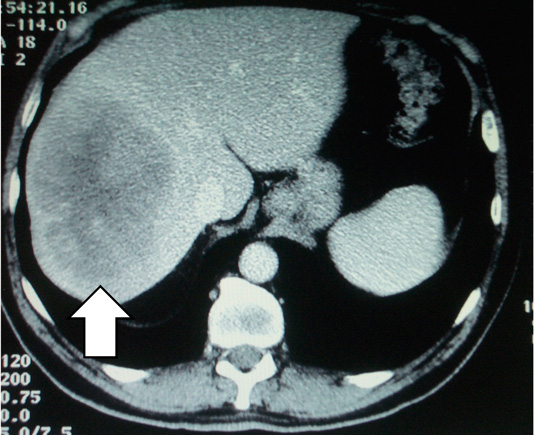

These CT scans show a secondary deposit in the liver from a cancer of the colon, before chemotherapy (left) and after chemotherapy (right). The patient then underwent surgery, but the significant shrinkage made for a lesser operation.